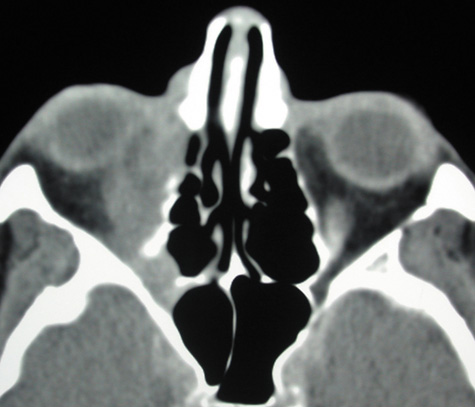

Magnetic resonance imaging (MRI) is purported to be more useful than CT in the diagnosis of preseptal cellulitis. It is less reliable at diagnosing the subtle signs of muscle enlargement and periscleritis and thus is not as useful in differentiating orbital cellulitis from other inflammatory orbital diseases.71 On MRI with gadolinium contrast, orbital cellulitis may show a smearing or linear streaking of the normal fat shadows on T2-weighted images. MRI is excellent for demonstrating localized fluid collections such as abscesses. It is not helpful in distinguishing a transudate from an exudate, because both appear liquid and are of low intensity on T1-weighted images and bright on T2-weighted images (Fig. 19).

Fig. 19. Magnetic resonance image of preseptal cellulitis with anterior abscess formation.